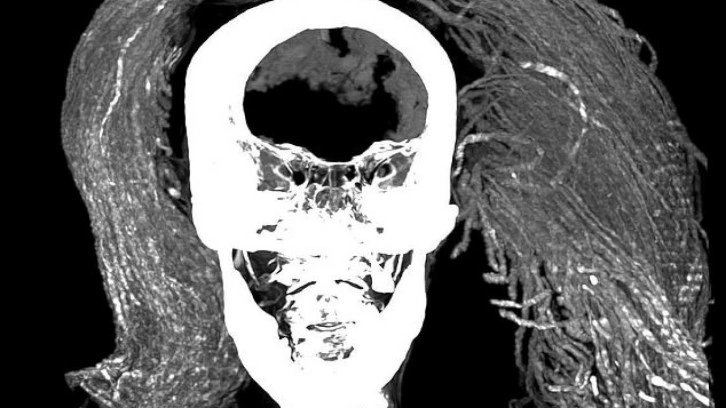

Frontiers in Medicine adlı hakemli dergide bugün (2 AÄŸustos) yayımlanan araÅŸtırmayı yürüten ekip, bilgisayarlı tomografi taraması ve X ışını kristalografisi gibi geliÅŸmiÅŸ yöntemlerle kadının derisini, saçını ve peruÄŸunu inceledi.Â

Bilim insanları kadının yaklaşık 1,55 metre boyunda olduÄŸunu ve muhtemelen 48 yaşında öldüğünü tespit etti. Kadının ölüm nedeni saptanamadı ancak orta derecede artritten muzdarip olduÄŸu bulundu.Â

Ayrıca mumyanın bütün iç organlarının yerinde durduğunu söyleyen araştırmacılar bunun alışmadık bir şey olduğunu ifade ediyor. Kahire Üniversitesi'nden çalışmanın ortak yazarı Dr. Sahar Saleem şöyle diyor:

Yeni Krallık'taki (MÖ 1550 - MÖ 1069) klasik mumyalama yönteminde kalp hariç tüm organlar çıkarıldığı için bu bana sürpriz oldu.

AraÅŸtırmacılar bu durumun düşük veya orta gelirli kesimlere ait mumyalarda görülebildiÄŸini fakat sözkonusu kadının daha üst sınıfa ait olduÄŸuna dair bulgular edindiklerini söylüyor.Â

Mumyalama iÅŸleminde ardıç ve tütsü gibi pahalı maddelerin kullanıldığını tespit eden ekip, bunun kadının önemli biri olduÄŸuna iÅŸaret ettiÄŸini belirtiyor.Â

Kadının peruğunda da bu maddeleri saptayan araştırmacılar, saçında da kına olduğunu kaydediyor.

Bu kanıtların özensiz bir mumyalama yapıldığı teorisiyle çeliştiğini söyleyen ekip, kadının ifadesinin nadir görülen, ani bir ölüm sertliği biçiminden kaynaklanabileceğini öne sürüyor.

Ölüm sertliği, kişinin ölümünden sonra vücudun katılaşmasını ifade ediyor. Araştırmacılar, kadının acı içinde çığlık atarak ölmüş olabileceğini savunuyor.

Bilim insanları kadının ölümünden sonraki 18 ila 36 saat içinde, vücudu gevşemeden veya çürümeden önce mumyalanmış ve bu yüzden ağzının açık kalmış olabileceğini düşünüyor.

Dr. Saleem, "Açık aÄŸzın, acılı bir ölüm ya da duygusal stresten kaynaklanabileceÄŸini ve kadavra spazmının yüzünü ölüm anındaki görünümünde dondurduÄŸunu öne sürüyoruz" diyerek ekliyor:Â

Mumyalama işlemini yapanların ağzı kapatamayıp kasılmış cesedi çürümeden ya da gevşemeden önce mumyalaması, ölümden sonra ağzın açık kalmasına yol açmış olabilir.